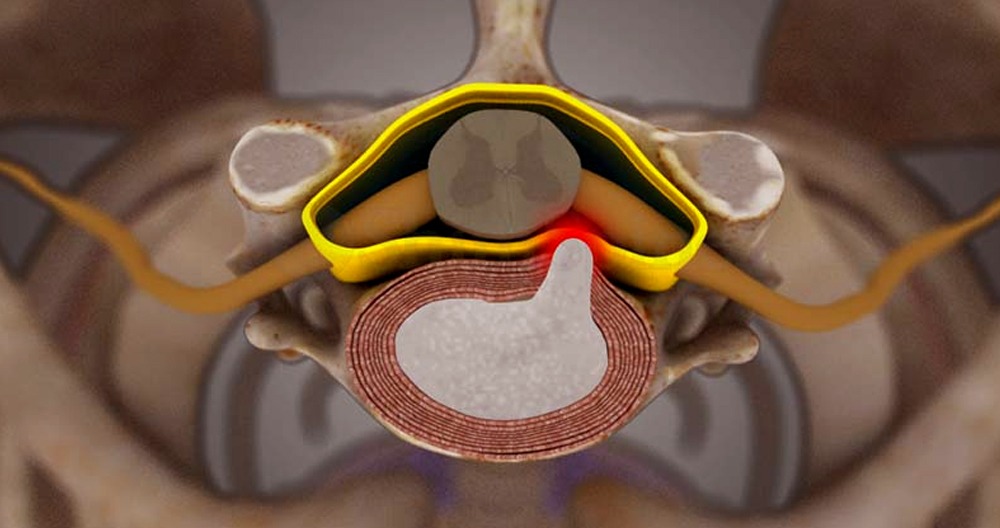

A gel-like substance is found in the middle of disks between vertebrae. The gel is kept contained in the outer portion of a disk by fibrous cartilage. Gel can pop out of the outer layer if it is split or tears. This is how a disk can become herniated. A herniated disc is also known as a “ruptured” disk or a slipped disk. It can be compared to a jelly doughnut with its filling squirted out.

The cervical spine has 6 intervertebral disks. Each cervical disc is located between two adjacent vertebrae (one below and one above) to cushion the vertebral bodies. They also help to distribute the load from the neck and head. There are two basic components to a disc.

- Annulus fibrosus. The outer layer of the disc is made up of concentric collagen fibers. This makes it strong enough to protect its soft inner layer. The spine’s heavy loads are absorbed by the annulus fibrosus.

- Nucleus pulposus. This gel-like interior is made up of a loose network fibers that are suspended in mucoprotein gel, and then protected by the annulus fibrisus. Additional cushioning and flexibility are provided by the nucleus pulposus, which provides additional mobility.

A herniated disk is when the disc’s outer layer breaks down and some of the nucleus pulsus leaks into it. The most painful part of a herniated disc is when the nucleus pulposus (which contains inflammatory proteins) leaks from the disc onto the nerve root. A herniated disk may also leak onto the spinal cord.

A Cervical Herniated Disk Is Severe

An intervertebral disk is a cartilaginous structure that consists of three components: an outer annulus fibrosus, inner nucleus pulposus and endplates. These are used to anchor the discs to adjacent vertebrae. When part or all the nucleus pulposus protrudes into the annulus fibrosus, disc herniations can occur. This can happen either acutely or chronically. Chronic herniations are caused by the intervertebral disk becoming degenerated and desiccated during the natural aging process. Symptoms of gradual or insidious onset tend to be milder. Acute herniations, on the other hand, are usually the result of trauma. The nucleus pulposus is forced through the annulus fibrosus. A sudden onset of severe symptoms will be more common in acute herniations than in chronic.

Herniated discs are caused by a combination mechanical compression of nerves by the bulging nucleus, and an increase in inflammatory cells. Microvascular damage can be caused by compression forces.

Posterolateral herniations are more common because the annulus fibrosus is thinner and does not have the support of the posterior longitudinal ligament. Radiculopathy can occur in the dermatome associated with radiculopathy due to the close proximity of the herniation and the traversing cervical nerve roots.